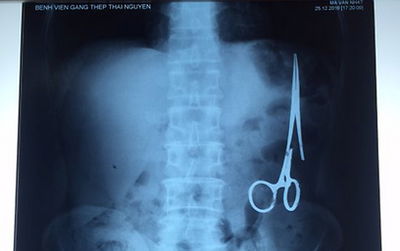

הסתובב 18 שנה עם מלקחיים בתוך הבטןדניאל הרץ|03.01.17|2כאב בטן קל בגללו הגיע החולה לבית החולים חשף כי במהלך הניתוח שעבר לפני 18 שנה נשכחו בבטנו מלקחיים רפואיות שהספיקו כבר להחליד. הן הוצאו בניתוח שנערך מיד (מעניין)